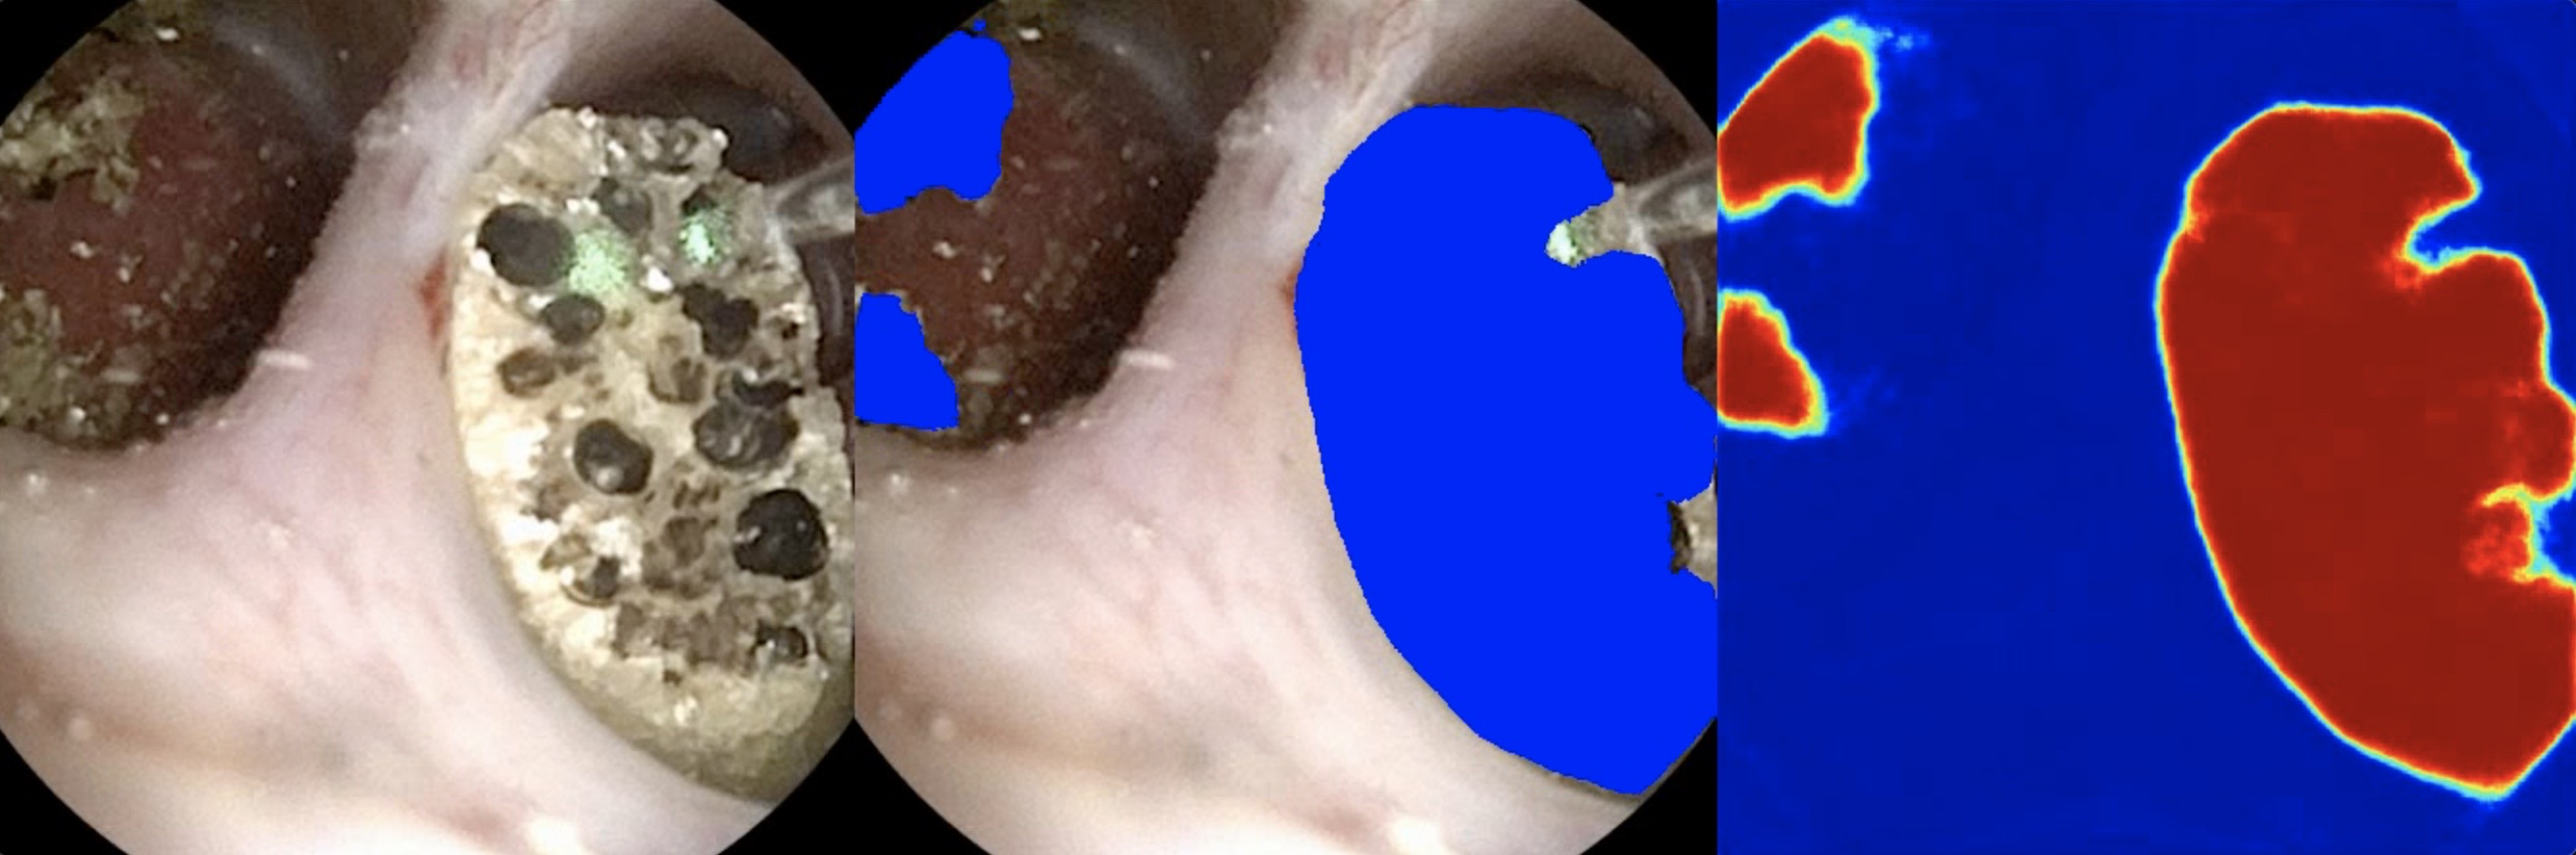

Additionally, we have unlabeled videos in our dataset as mock up examples of realistic videos that a deployed model would see. Shown in Figure 5 for a representative unlabeled video in our dataset, we created segmentation predictions for these videos using our video processing script described above as a proof-of-concept for the visual overlay that we intend to deploy in operating rooms where our model will receive real-time and “in-step” video frames from the endoscopic hardware.

Refer to caption

Figure 5: Sample output frame for a representative unlabeled input video from our dataset with our best U-Net++ model. This video has no ground truth annotation at the time of publication. Debris collects in the left duct and is still segmented by the model.

To deploy our high-performing model for surgical use in operating rooms, we will extend our video processing script to receive “in-step” frame-by-frame video input from a video capture card connected via DVI/HDMI to the endoscopic hardware. Then, we will output the side-by-side frames, as in Figure 5, to an adjacent monitor to assist physicians in surgery. Developing such a system will allow us to investigate further goals, such as monocular depth prediction which might prove critical in automation [18].

In practice, the problem domain also requires the segmentation of kidney stones after they have been surgically broken down into smaller pieces. The current dataset has been developed to support the segmentation of only whole kidney stones. Further development will include expansion of another section of the dataset where, as a surgeon breaks stones apart, the debris fragments will still be labeled by our model. In Figure 5, our model already segments clumps of debris; however, our future goal is finer granularity via an instance segmentation method [20].